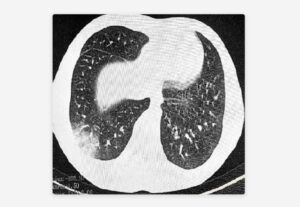

La enfermedad de la bronquitis obliterante se produce cuando las pequeñas vías que llevan aire a los pulmones sufren inflamaciones